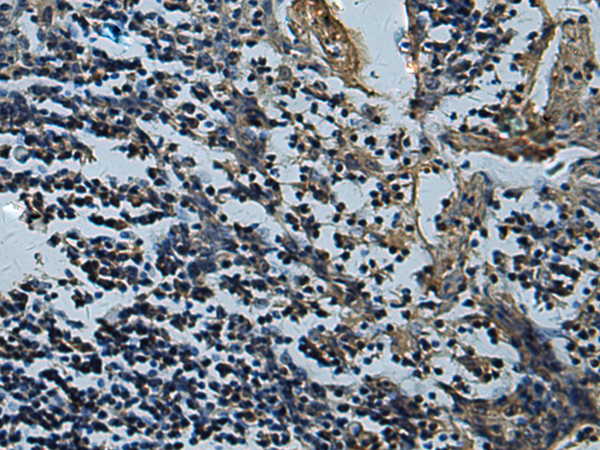

IHC positive control: |

Human thyroid cancer and Human tonsil |

IHC Recommend dilution: |

50-200 |